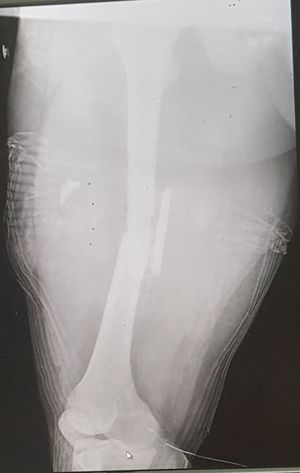

femore fracture

Emergency

Fracture